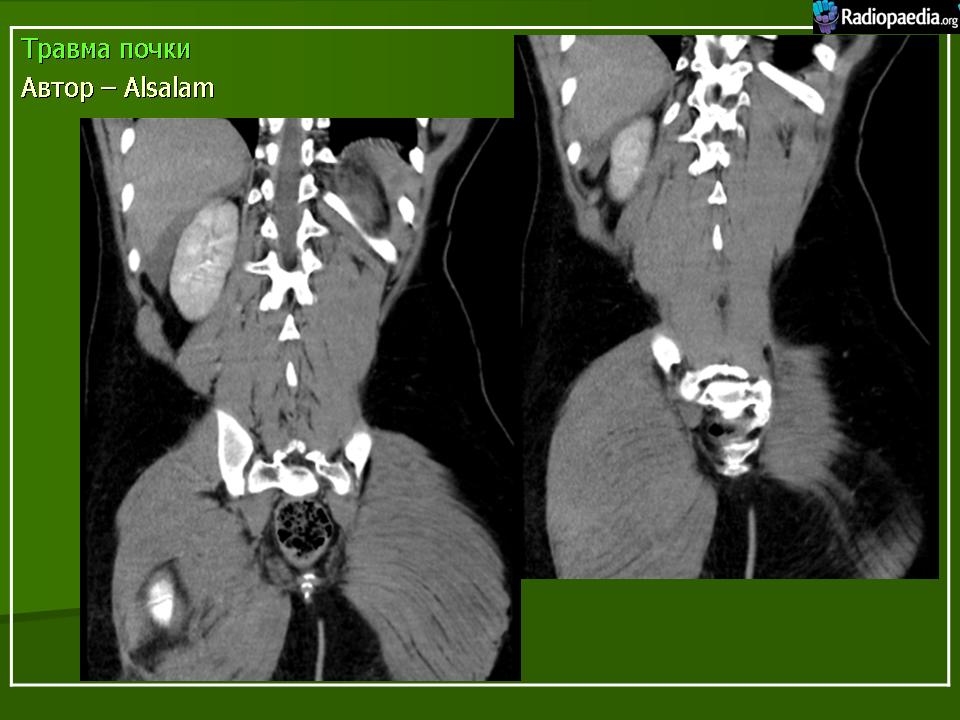

Разрыв почки

Почечная травма

Травма почки.